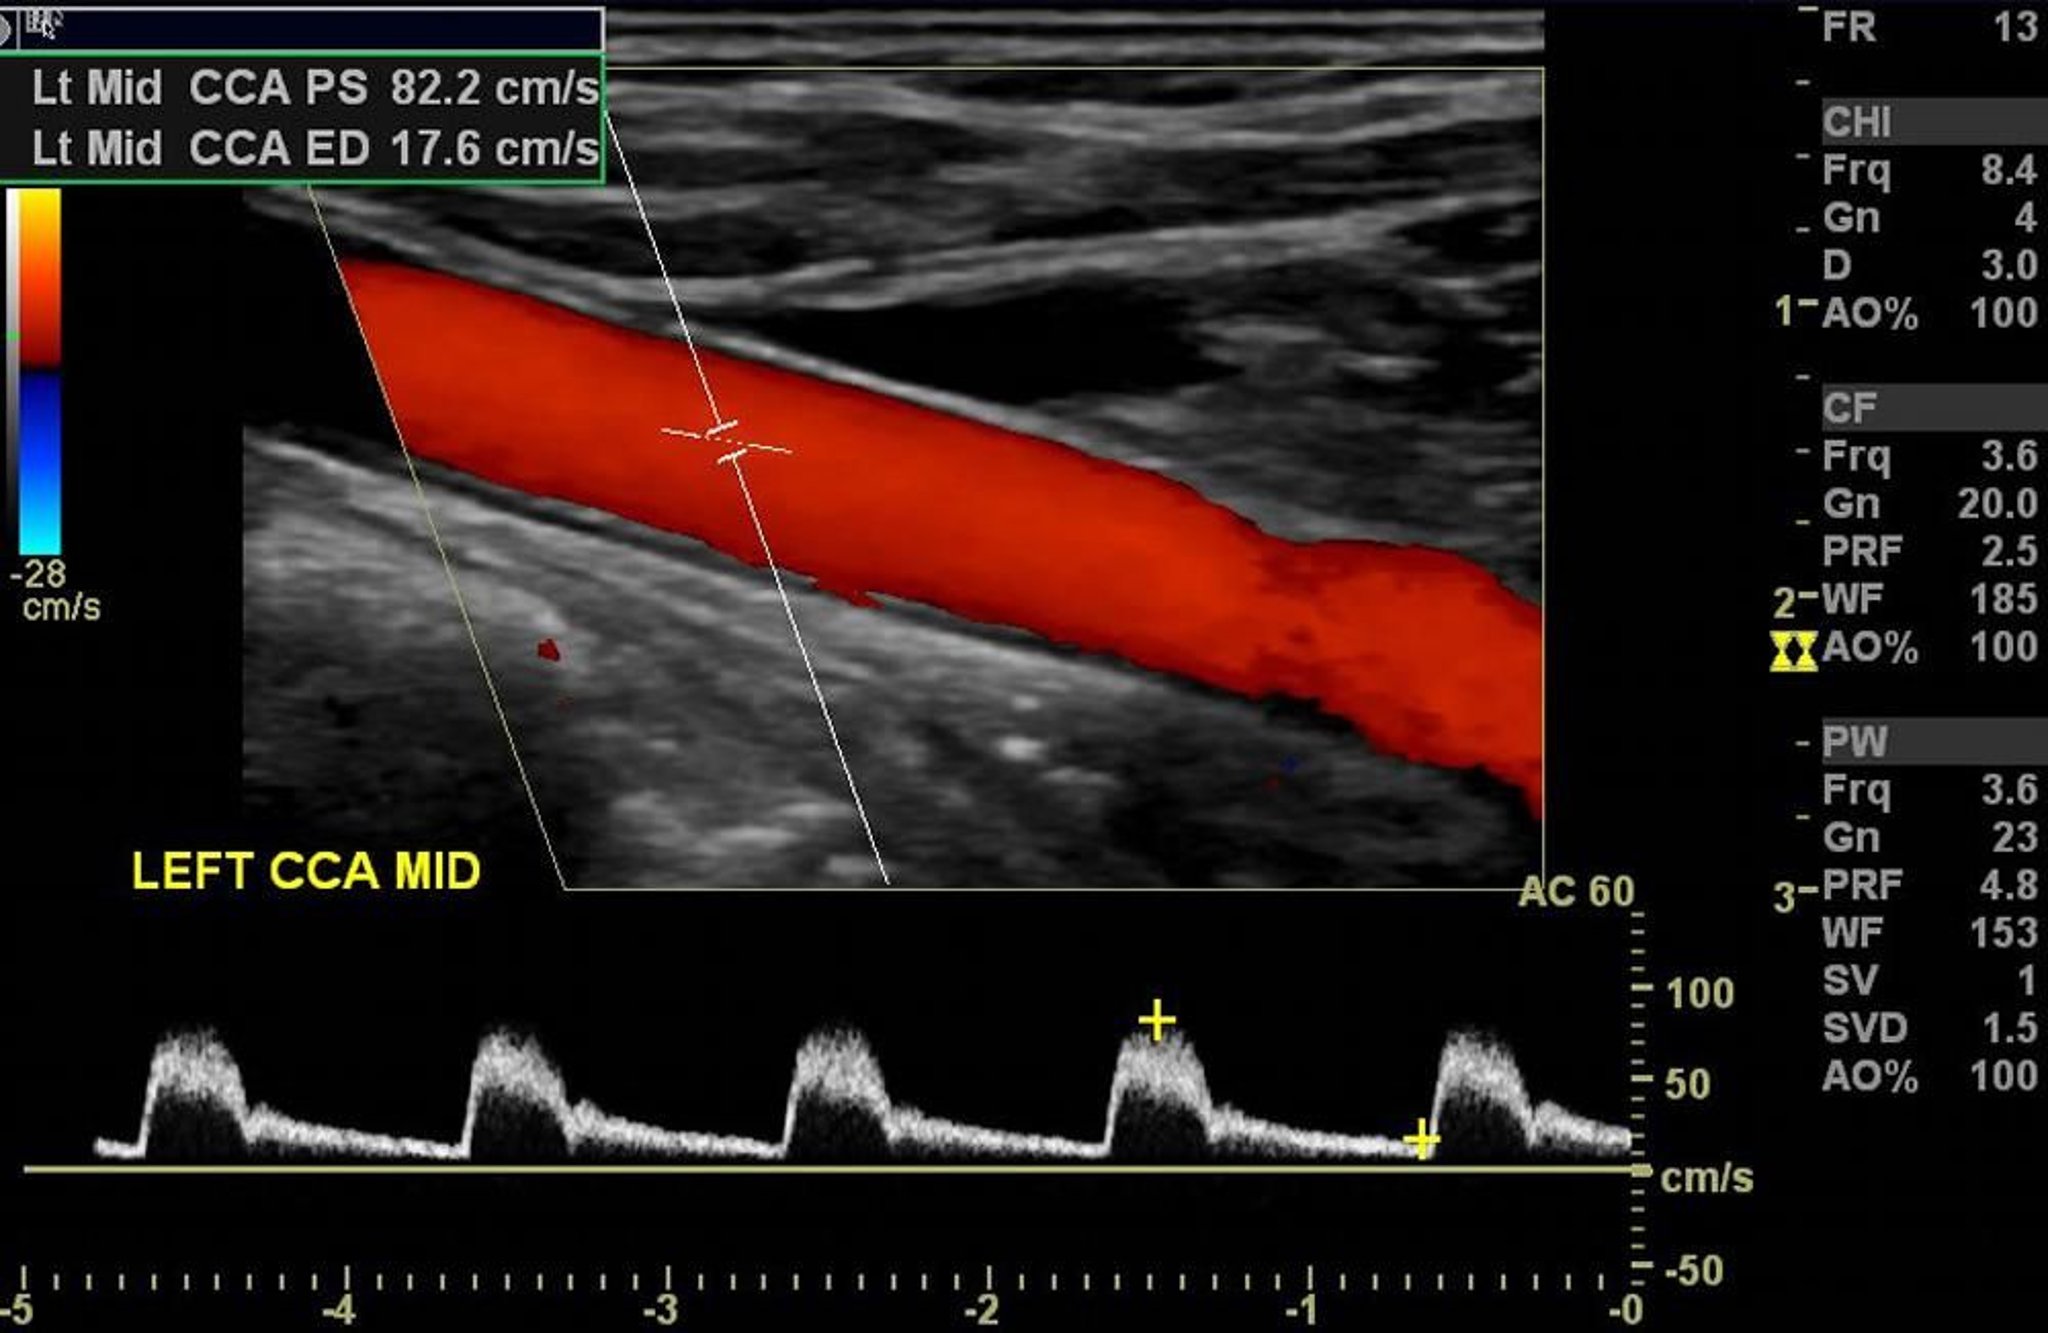

L'ecocolordoppler dell'arteria carotide sinistra mostra un flusso arterioso normale senza stenosi significativa.

Image courtesy of Hakan Ilaslan, MD.